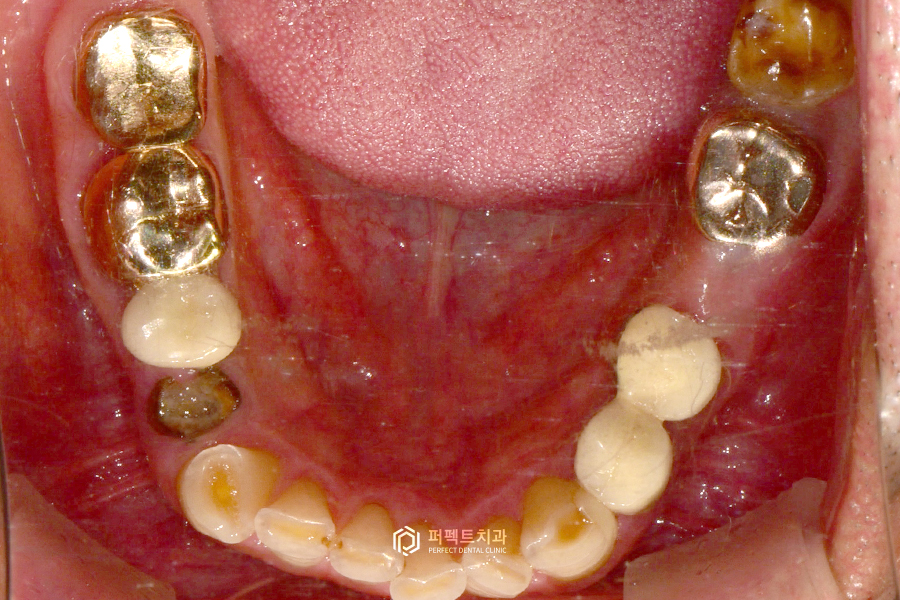

아랫니 같은 경우도 뿌리만 남은 부분들을 임플란트를 통해 수복을 했고, 자연치아는 쓸 수 있는 경우여서 치료를 하지 않고 그대로 사용하고 있는 경우입니다.

치료 후 사진을 보시면 임플란트가 오른쪽 위에 2개, 왼쪽에 1개, 아래 2개 이렇게 치아가 없는 부위를 수복했습니다. 임플란트가 없는 왼쪽 어금니 부분은 기다렸다가 추후에 식립을 진행했습니다.

이렇게 어금니는 총 7개의 임플란트를 식립했고, 앞니 보철과 아랫니 부분도 꼭 해야하는 부분은 다시 재치료를 했습니다.